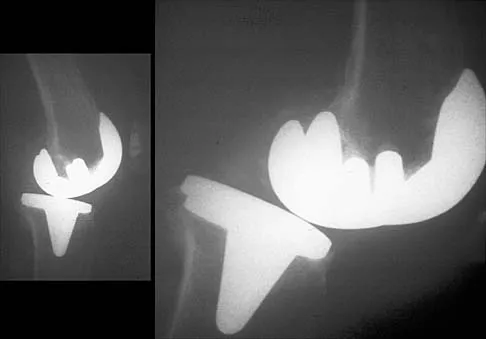

Figure 20 shows the resting and stress radiographs of a patient who has had pain and feelings of instability after undergoing a total knee arthroplasty 1 year ago. Which of the following ligaments is not functional and is therefore responsible for the patient's symptoms?